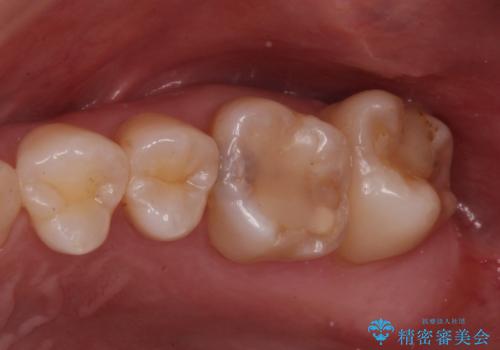

奥歯の治療の劣化が気になる。ザラザラしている

- 奥歯がザラザラして欠けている気がするとの事で来院。

古いプラスチックの詰め物がされていて、少し欠けていました。

拡大鏡下で古いプラスチックを除去して虫歯がないことを確認して

e-maxインレーにて治療しました。